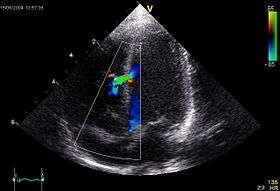

The diagnosis of pulmonary atresia can be done via the following exams/methods: an echocardiogram, chest x-ray, EKG and an exam to measure the amount of O

2in the body.[6]